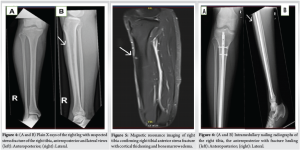

A 26-year-old male professional football player presented to us in the outpatient clinic in July 2024, on wheelchair with the complaint of bilateral shin pain over the past 4 months, localized on the anterior aspect of both legs. The pain was initially mild and worsened during playing football, followed by a constant pain on the left side, which started affecting his sleep and his routine activities. In addition, he complained of mild discomfort on his right leg. He had no history of any recent trauma and other joints or extremity pain in the past, but claimed an increase in intensity of pain while playing football. He had previously used anti-inflammatory medications, calcium, and activated cholecalciferol supplements, and underwent 8 sessions of physiotherapy. During physical examination, inspection revealed normal gait and normal alignment of both lower limbs and there was mild tenderness left mid leg and absent tenderness on the right side on palpation. The range of motion of associated joints and spine was within normal limits. Sensory and motor of each lower limb was normal and comparable. Plain X-ray of left leg (Fig. 1) demonstrated abnormal density in the middle left tibial shaft anteriorly, while right tibia X-rays were inconclusive. Based on X-ray results, the possibility of osteomyelitis in the left tibia was considered, and all inflammatory markers (C-reactive protein, erythrocyte sedimentation rate) were sent, revealing normal levels, which excluded any infections. In addition, endocrine/metabolic workup (Vitamin D, Calcium, parathyroid hormone, thyroid-stimulating hormone, and testosterone) was done and was in normal limits. A computed tomography (CT) scan confirmed left tibia anterior shaft stress fracture (Fig. 2). After reviewing the patient’s history, review of all medications, and thorough examination, including a careful biomechanical assessment and scanning results, a diagnosis of a stress fracture in the left tibia was made. Due to a lack of improvement with trial of conservative management on the left side over the past 4 months, a decision was made to proceed with intramedullary nailing on the left tibia while continuing conservative treatment on the right side, as the X-rays were unremarkable. Post-operative recovery of the patient was unremarkable, and he was allowed weight bearing as tolerated under the supervision of a physiotherapist (Fig. 3). At 3 months, he presented to the outpatient clinic as a follow-up case, with minimal symptoms in his left tibia. However, he expressed ongoing discomfort and mild pain in his right leg, which he claimed partly alleviated with analgesics and avoiding exertional activities. Due to ongoing pain on his right side, right leg X-rays were performed that revealed suspicion of anterior cortex stress fracture (Fig. 4). Consequently, an MRI was performed, which displayed a low signal on T2-weighted imaging with cortical thickening and bone marrow edema, confirming anterior tibial stress fracture (Fig. 5). Keeping in view his previous history, present imaging results and delayed diagnosis, he was decided to undergo intramedullary nailing right tibia. At the 4-month follow-up after the surgical fixation of his right tibial stress fracture, the patient was fully ambulant without any support. Follow-up radiographs of the right leg showed an evidence of fracture healing and nail in situ (Fig. 6). By 6 months, the patient returned to competitive football without restrictions.